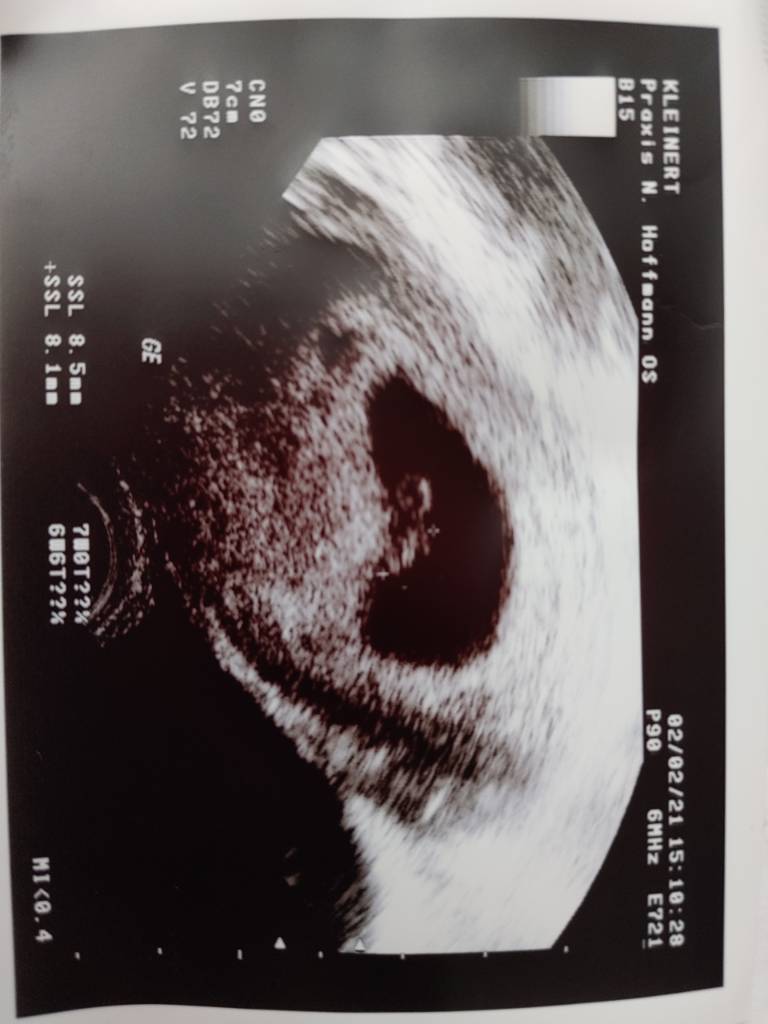

Super cieszę się, że wszystko okej <3Hej. Melduje sie wszystko jest okej. Krwawienie to ona nje wie skad. Mam brac dalej 3 razy dziennie luteine. Serduszko juz bilo ale nie slyszalam. 7+0 z usg wychodzi. [emoji178]Zobacz załącznik 1233818